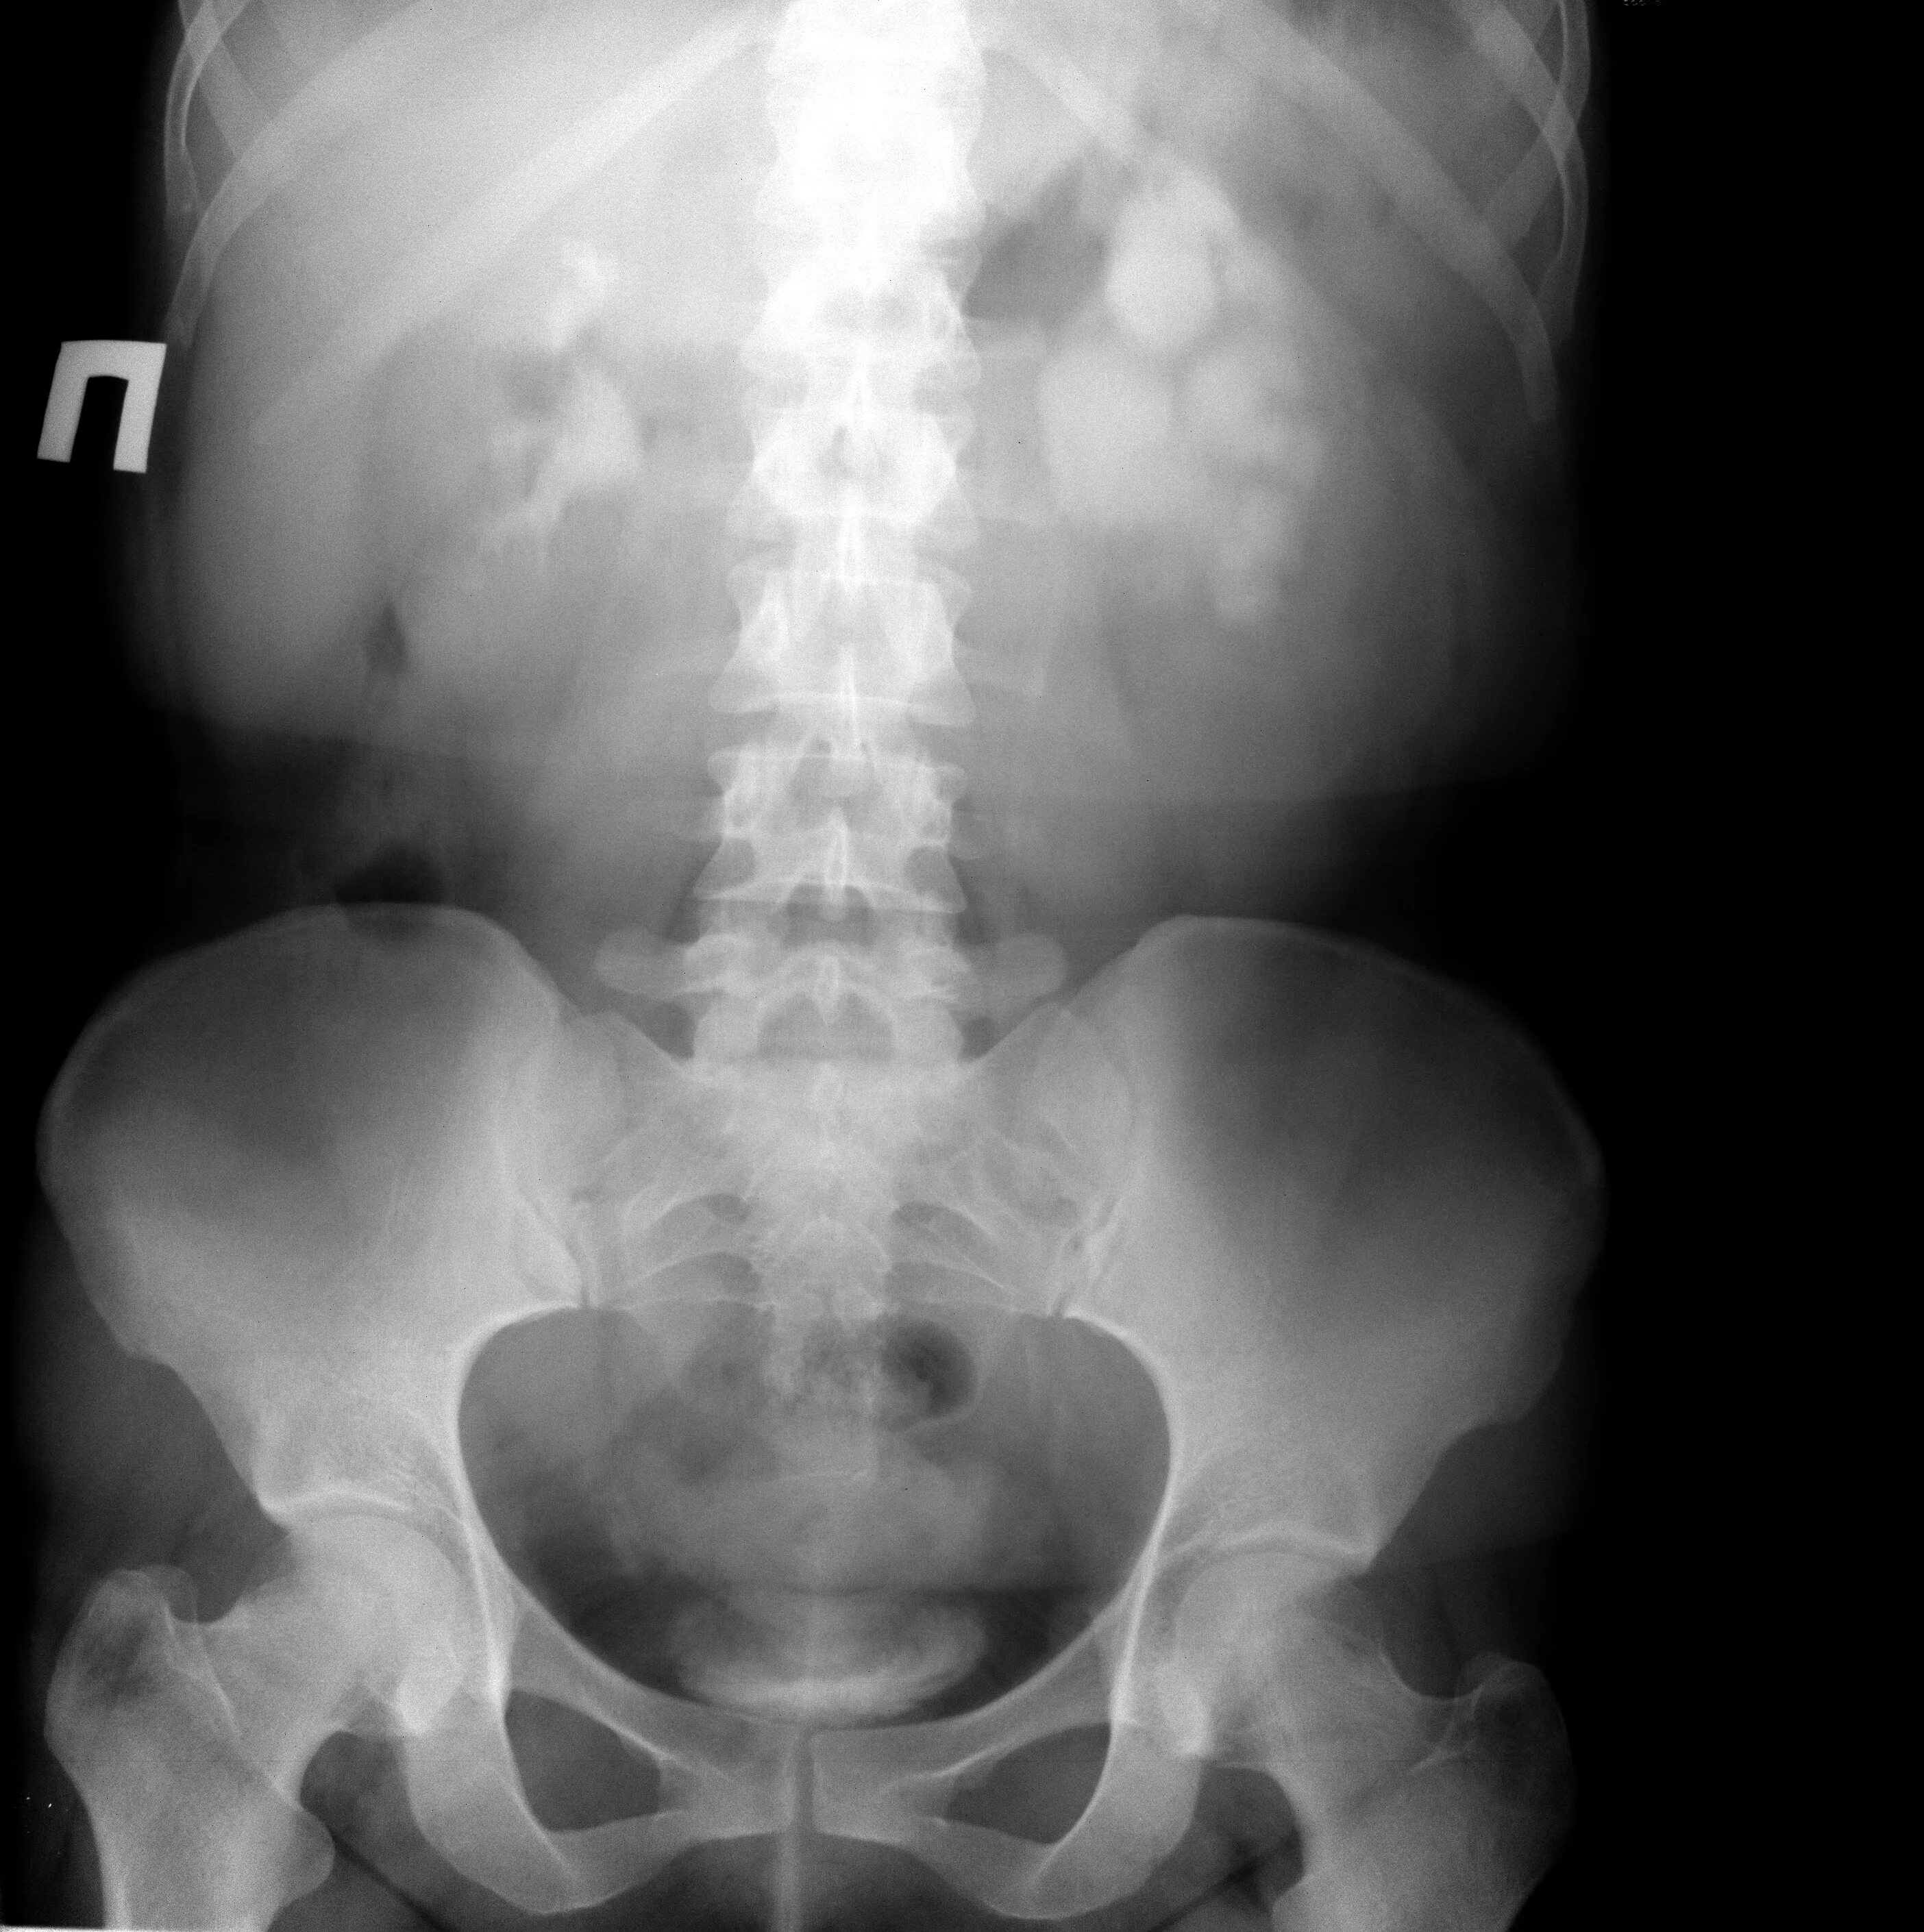

Гидронефроз 1 степени